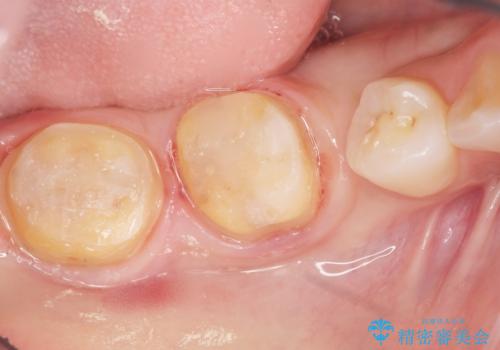

矯正せずに早く治したいという強いご希望とう蝕があることから、セラミッククラウンによる補綴治療で隙間を閉じることにしました。

クラウンの種類:オールセラミッククラウン スタンダード